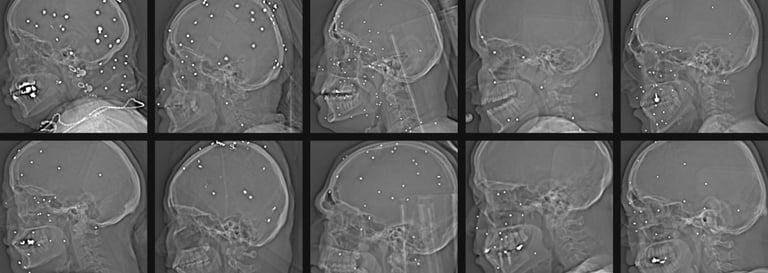

Vittnen och familjer i Iran har beskrivit hur vissa barn sköts när de var på väg hem, tillfälligt anslöt sig till sina föräldrar eller observerade demonstrationer. Andra unga människor hamnade i urskillningslös beskjutning i bostadsområden och på marknadsplatser när säkerhetsstyrkor öppnade eld med automatkarbiner, hagelgevär och andra dödliga vapen. Videomaterial och rättsmedicinska bilder som verifierats av internationella medier visar skottskador och kroppar av minderåriga tillsammans med andra offer för nedslaget.